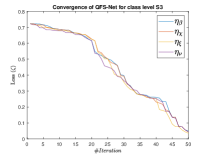

The suitable tailoring of the phase angle in the Hadamard gate advocates the stability of the QFS-Net or its convergence which is very crucial for self-supervised networks where the loss function (here error function) is dependent on the interconnection weights. Hence, the phase angles are evaluated using and as given in Equations 18 and 21, respectively. It is worth noting that the qutrit based quantum neural network provides faster convergence compared to the classical neural networks. This is due to the fact that whereas the classical neural networks are formed using the multiplication of input vector and the weight vector guided by an activation function, the quantum-based networks incorporate the frequency components of the weights and their inputs thereby enabling faster convergence of the network states. This inherent novel feature of the quantum neural networks facilitates the qutrit based fully self-organized quantum algorithm to be employed in QFS-Net to converge super-linearly, as shown in Figure 3. The loss function cum QFS-Net network error function is defined on quantum measurement in the following way.

where, represents the true interconnection weight terms of the inter-connection weights as expressed using the Hadamard gate () at an instance (). is a coherent error function of and . Convergence analysis of the proposed qutrit-inspired QFS-Net is provided in Appendix Section -A and demonstrated experimentally with qubit embedded QIS-Net [39] as shown in Figure 3. It can be summarized that the convergence of the QFS-Net is faster than that of the QIS-Net and also follows super-linearity. This claim is also substantiated by the number of iterations required to converge for each image slice in QFS-Net and QIS-Net as illustrated in Figure 4.